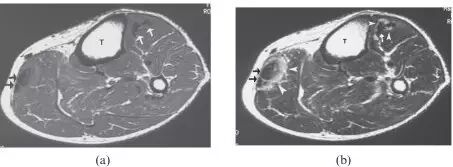

![]()

图8.26岁女性多发性肌炎,呈现双侧下肢疼痛和肌肉无力。(a)大腿的轴向T2加权的MR图像显示在股外侧肌,中间肌,内侧肌和股直肌(箭头)的异常,广泛的羽状水肿。注意保持正常的肌肉结构。T1加权成像(未显示)在受影响的肌肉中未显示信号改变或萎缩,或在此情况下有助于诊断。(b)两腿的冠状动脉脂肪抑制的T2加权的MR图像还在小腿的肌肉(箭头)中显示广泛的水肿信号。右腓肠肌的内侧头显得幸免(箭头)。